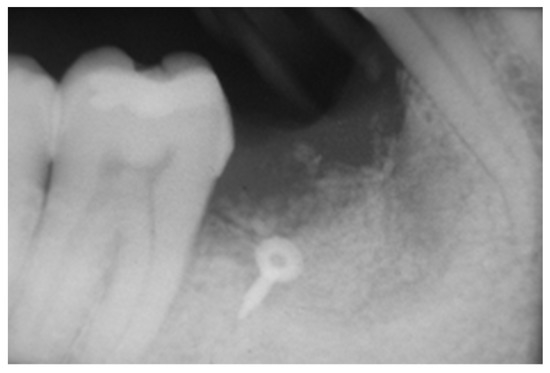

2.3. Peri-Implant Bone Levels Assessment